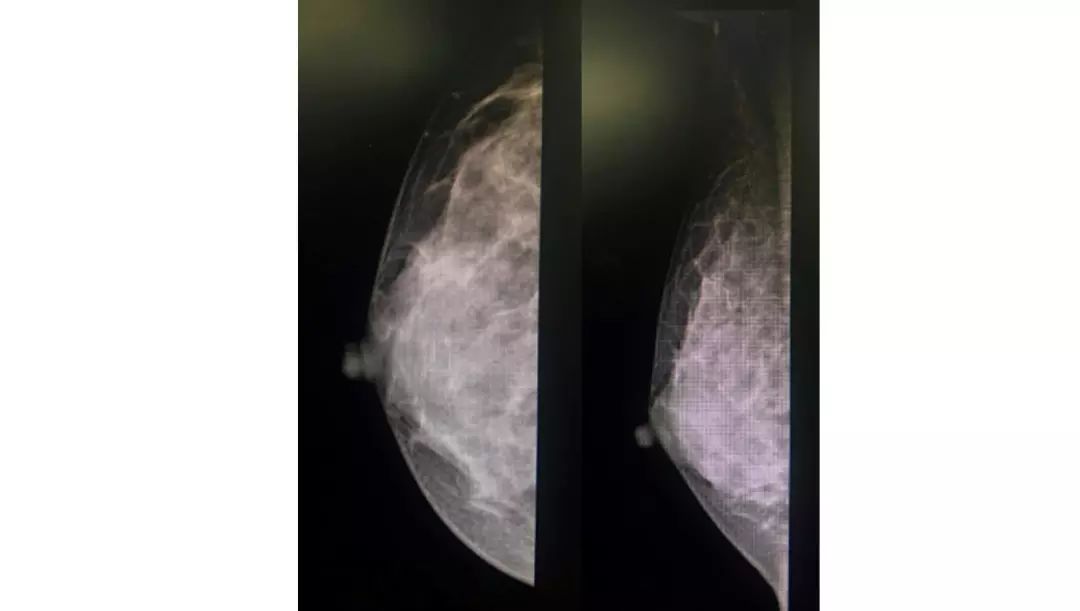

图2 2018年8月27日乳腺钼靶

2018年8月15日行乳腺超声检查:右乳外上11mm×9mm低回声区,边界不清晰,内部回声不均匀,未见明显血流信号。右腋下见淋巴结7mm×4mm,皮质稍增厚。超声诊断:双乳小叶增生,右乳低回声(BI-RADS 4B),右腋下淋巴结。2018年8月27日行双乳钼靶检查:双乳未见明显异常(BI-RADS 1)。